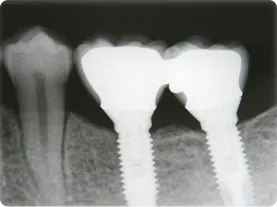

症例1/

臼歯2本

- 治療期間

- 10ヶ月

- 費用

- 90万円(税込)

治療前

治療後

レントゲン画像